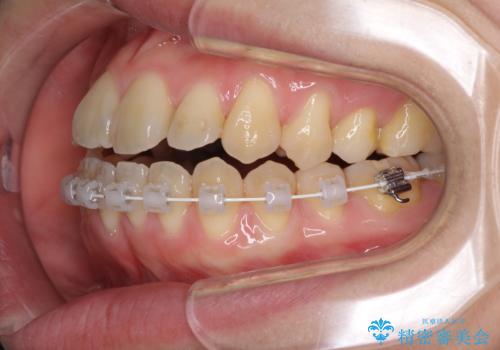

- ハーフリンガル

目立ちにくい装置での治療をご希望とのことで、上顎が裏側装置、下顎が表側装置のハーフリンガルにより矯正治療を行うこととしました。

下顎の歯列全体を後方に動かす場合、さまざまリスクを伴うため慎重に行う必要があり、さらには移動量に限界があるため、治療計画は無理のないものとしなければなりません。

下顎左右の奥にアンカーボルトを使用して、無理のない範囲で後方に移動させ、きれいに仕上げることができました。